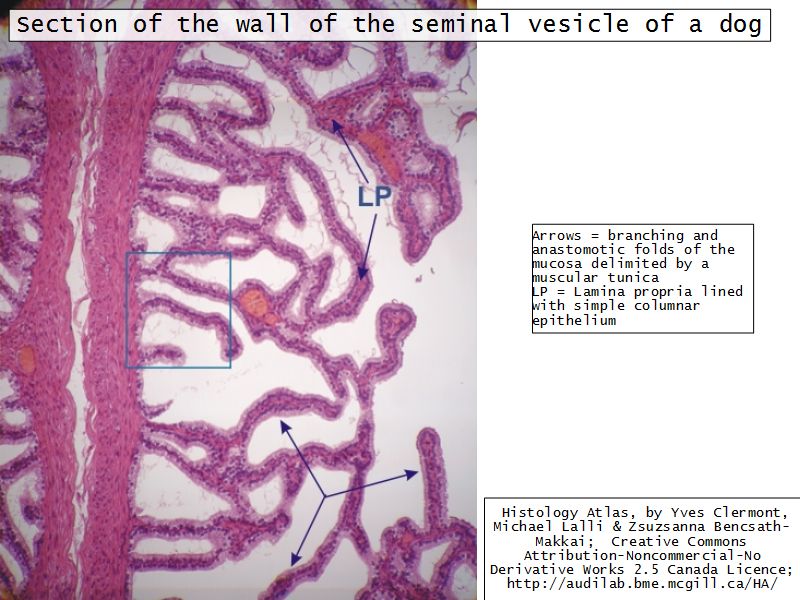

Vesicula seminalis

Slide 81Vesicula seminalis

- Mucosa

- Epithelium

- Lamina propria

- Muscle layer

Mucosa

- Lumen

- Irregular

- Store secretions

- Pseudostratified columnar epithelium

- Lamina propria

- Contains AVL

- Folded mucosa ^^ surface area

Muscle layer

- Inner circular

- Outer longitudinal